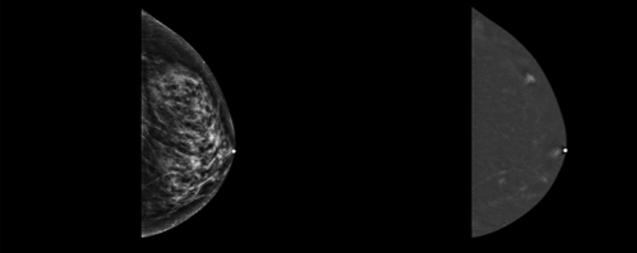

L’IA en échocardiographie 51 Quand les robots prennent la sonde